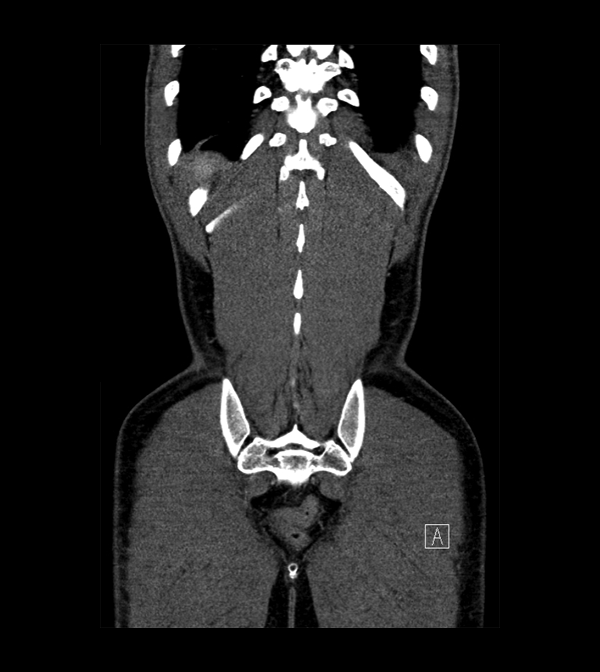

Body

Covers abdominal CT anatomy.